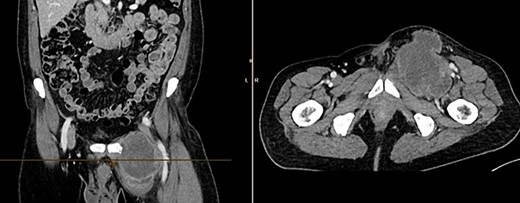

The CT of the abdomen showed a highly suspicious malignant mass in the left groin area (Fig 3). Additionally, nearby satellite lesions were detected, interpreted as lymph nodes. During a more thorough physical examination, a hazelnut-sized, highly suspicious malignant lesion was identified on the glans penis. Upon detailed anamnesis, the patient reported a previous circumcision surgery with carcinoma detection.

Finding from CT of the abdomen: highly suspicious malignant mass in the left groin area, with nearby satellite lesions, DD lymph nodes.